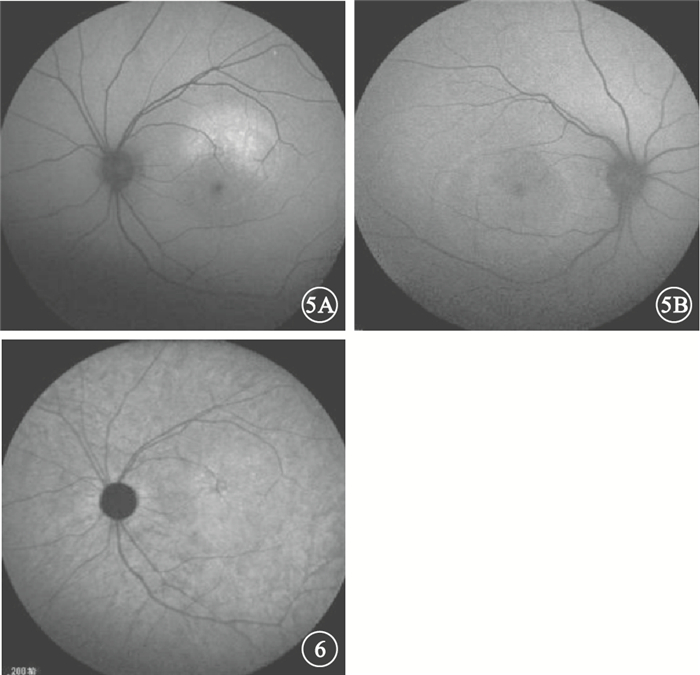

慢性CSC 34只眼中,與FFA檢查可見的滲漏點對應處BLAF表現以點狀或片狀強熒光(圖 5A)為主,其次是無異常改變者,表現為點狀、片狀弱熒光(圖 5B)或斑駁熒光者較少。可觀察到神經上皮層脫離(圖 5B)14只眼,占41.2%。其中,表現為圓形或橢圓形弱熒光9只眼,占65.3%;表現為強熒光5只眼,占35.7%。IRAF表現以點狀、片狀弱熒光或斑駁熒光(圖 6)為主,其次為點狀或片狀強熒光,較少數無明顯改變。可觀察到神經上皮層脫離僅3只眼,占8.8%;均表現為類圓形弱熒光(表 2)。

圖5

慢性CSC患眼BLAF像。5A.圖 2A同眼,與FFA檢查可見的滲漏點對應處表現為點狀強熒光;5B.圖 2B,與FFA檢查可見的滲漏點對應處表現為片狀弱熒光,周圍可見類圓形神經上皮層脫離??圖 6?圖 2A同眼IRAF像。與FFA檢查可見的滲漏點對應處表現為斑駁熒光

圖5

慢性CSC患眼BLAF像。5A.圖 2A同眼,與FFA檢查可見的滲漏點對應處表現為點狀強熒光;5B.圖 2B,與FFA檢查可見的滲漏點對應處表現為片狀弱熒光,周圍可見類圓形神經上皮層脫離??圖 6?圖 2A同眼IRAF像。與FFA檢查可見的滲漏點對應處表現為斑駁熒光

慢性CSC 34只眼中,與FFA檢查可見的滲漏點對應處BLAF表現以點狀或片狀強熒光(圖 5A)為主,其次是無異常改變者,表現為點狀、片狀弱熒光(圖 5B)或斑駁熒光者較少。可觀察到神經上皮層脫離(圖 5B)14只眼,占41.2%。其中,表現為圓形或橢圓形弱熒光9只眼,占65.3%;表現為強熒光5只眼,占35.7%。IRAF表現以點狀、片狀弱熒光或斑駁熒光(圖 6)為主,其次為點狀或片狀強熒光,較少數無明顯改變。可觀察到神經上皮層脫離僅3只眼,占8.8%;均表現為類圓形弱熒光(表 2)。

圖5

慢性CSC患眼BLAF像。5A.圖 2A同眼,與FFA檢查可見的滲漏點對應處表現為點狀強熒光;5B.圖 2B,與FFA檢查可見的滲漏點對應處表現為片狀弱熒光,周圍可見類圓形神經上皮層脫離??圖 6?圖 2A同眼IRAF像。與FFA檢查可見的滲漏點對應處表現為斑駁熒光

圖5

慢性CSC患眼BLAF像。5A.圖 2A同眼,與FFA檢查可見的滲漏點對應處表現為點狀強熒光;5B.圖 2B,與FFA檢查可見的滲漏點對應處表現為片狀弱熒光,周圍可見類圓形神經上皮層脫離??圖 6?圖 2A同眼IRAF像。與FFA檢查可見的滲漏點對應處表現為斑駁熒光